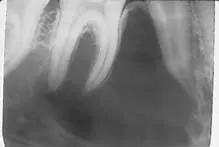

Radiographic examination revealed a solitary well-defined radiolucency in the right mandible (see film). The radiolucency appeared large with inter-radicular scalloping and well-defined borders. The lesion appeared to extend around and between the roots of the adjacent teeth. The roots of the teeth surrounded by the lesion appeared to exhibit an intact lamina dura and periodontal ligament space. The teeth adjacent to the radiolucency tested vital.

On a radiograph, the simple bone cyst appears as a solitary unilocular radiolucency with well-defined margins that exhibit a characteristic inter-radicular scalloping. The term scalloping refers to the borders of the lesion that curve and extend between the surfaces of adjacent tooth roots.

In a small number of cases, the simple bone cyst may appear as a multilocular radiolucency. Although most simple bone cysts measure less than 3 centimeters in diameter, the lesion size is variable and can range from 1 to 10 centimeters in diameter. The lamina dura and periodontal ligament space of the adjacent teeth appear intact. The simple bone cyst rarely displaces teeth, destroys roots, or perforates cortical bone.